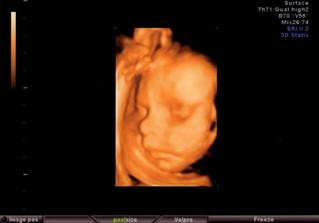

Ve středu 20.8.08 byla maminka s tatínkem v kině na muzikálu Mamma mia a já (malé miminko) jsem pařilo v bříšku až do rána. A na další den jsem se fotilo u pana doktora, ale o tom nic nevím, protože jsem po tak náročné noci celý den spinkalo. Alespoň si mě mohli pěkně vyfotit na 3D ultrazvuku. Změřili mi hlavičku a prý jsem se tatínkovi poved i když mě dělal po tmě

🙂.

Zatím mám takových 22 - 24 cm a vážím okolo 800 g.

Do obrazu se mi vejde už jen hlavinka.